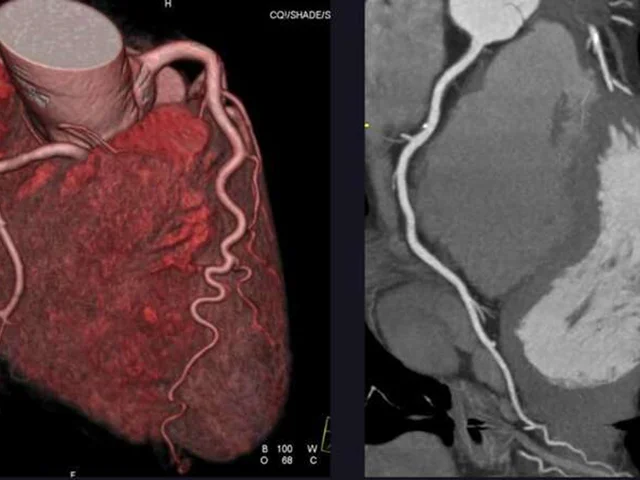

CT or Invasive Coronary Angiography in Stable Chest Pain

NEJM Evaluating Stable Chest Pain — An Evolving Approach